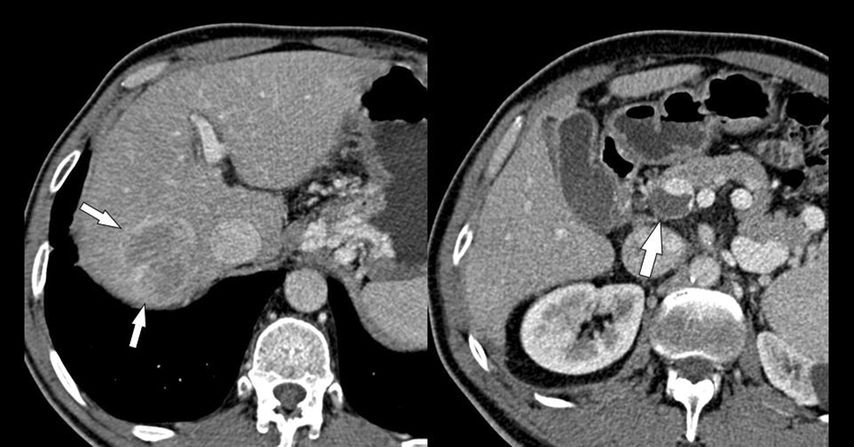

Abb. 4: HCC und PVT: Das HCC im rechten Leberlappen (kleine Pfeile links) hat keinerlei Verbindung zum (blanden) Thrombus im Pfortaderhauptstamm, der kein Kontrastmittel aufnimmt (großer Pfeil)

Zirrhose und „HCC mit Tumorthrombus“

Abb. 5: HCC mit Tumoreinbruch in die Pfortader: Die MDCT (koronale 3D-Rekonstruktion) zeigt den Kontrastmittel-aufnehmenden Tumor, der vom rechten Leberlappen in den rechten Pfortaderast vorwächst und diesen massiv aufweitet (Pfeile)

Die Bezeichnung „HCC mit Tumorthrombus“ ist irreführend und sollte nicht mehr verwendet werden, da es hierbei zu einem direkten Vorwachsen des HCC in die Pfortaderäste (u.U. bis in den Hauptstamm) kommt und nicht zur Bildung eines Thrombus. In der MDCT oder der MRT ist dafür typisch, dass man ein kontinuierliches Vorwachsen des HCC aus dem Parenchym in die Pfortaderäste erkennt. Der intravasale Tumoranteil weitet die Pfortader aus und zeigt ein Kontrastmittelenhancement wie der Tumor (Abb. 5), während ein blander Thrombus typischerweise keine Kontrastmittelaufnahme aufweist (Abb. 5). Der intravasale Tumoranteil muss daher auch wie ein Tumor behandelt werden und nicht wie eine Thrombose. Das American College of Radiology hat deshalb in seiner LI-RADS®-Guideline für die Beurteilung von hepatalen Knoten in der Zirrhose die KategorieLI-RADS TIV („tumor in vein“) geschaffen, um diese besondere Tumorentität von den HCC mit oder ohne PVT klar abzugrenzen.